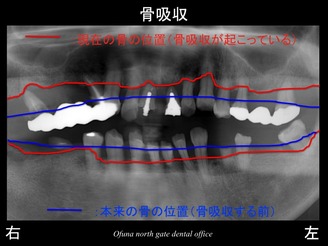

いつものように 骨吸収の状態を分かりやすくするために

骨吸収の状態を線で書いたのが以下のレントゲンになります。

青線が骨吸収を起こす前の骨の位置です。

赤線は、現在の骨の位置です。

さらに分かりやすくするために 骨吸収部位を赤色の領域で表しします。

骨吸収が非常に大きいのが分かります。